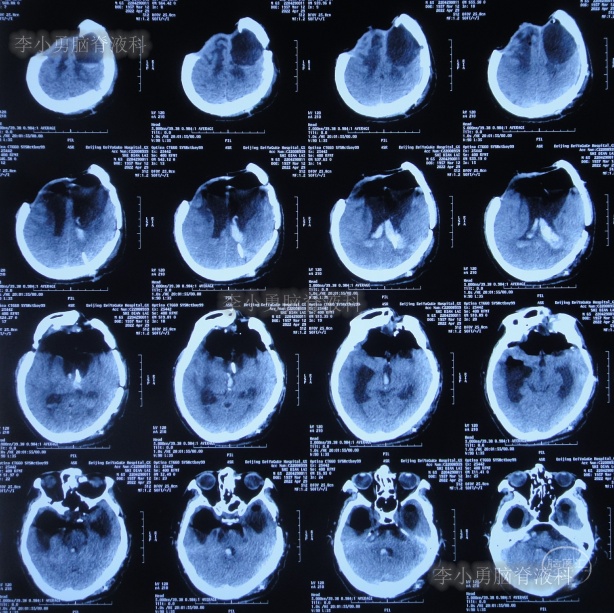

2013年1月22日(入院治疗83天),患者术区引流管引流液极少,复查头颅CT脑室较前稍有扩张,右侧骨窗张力仍较高(图-15),进行了侧脑室外引流术(右)+左额颞顶硬膜下引流管去除术+左顶硬膜外引流管去除术。

图-15:2013年1月22日头颅CT

2013年1月25日(入院治疗86天),查头颅CT示脑室有缩小(图-16)。

图-16:2013年1月25日头颅CT

2013年1月31日(入院治疗92天),查头颅CT示脑室进一步缩小,骨窗塌陷(图-18)。

图-18:2013年1月31日头颅CT

继续治疗1个半月,期间4次(2013年2月15日、2013年2月27日、2013年3月5日、2013年3月11日)查头颅CT(图-19、图-20、图-21、图-22)均示脑室在不断的变好。

图-19:2013年2月15日头颅CT

图-20:2013年2月27日头颅CT

图-21:2013年3月5日头颅CT

图-22:2013年3月11日头颅CT